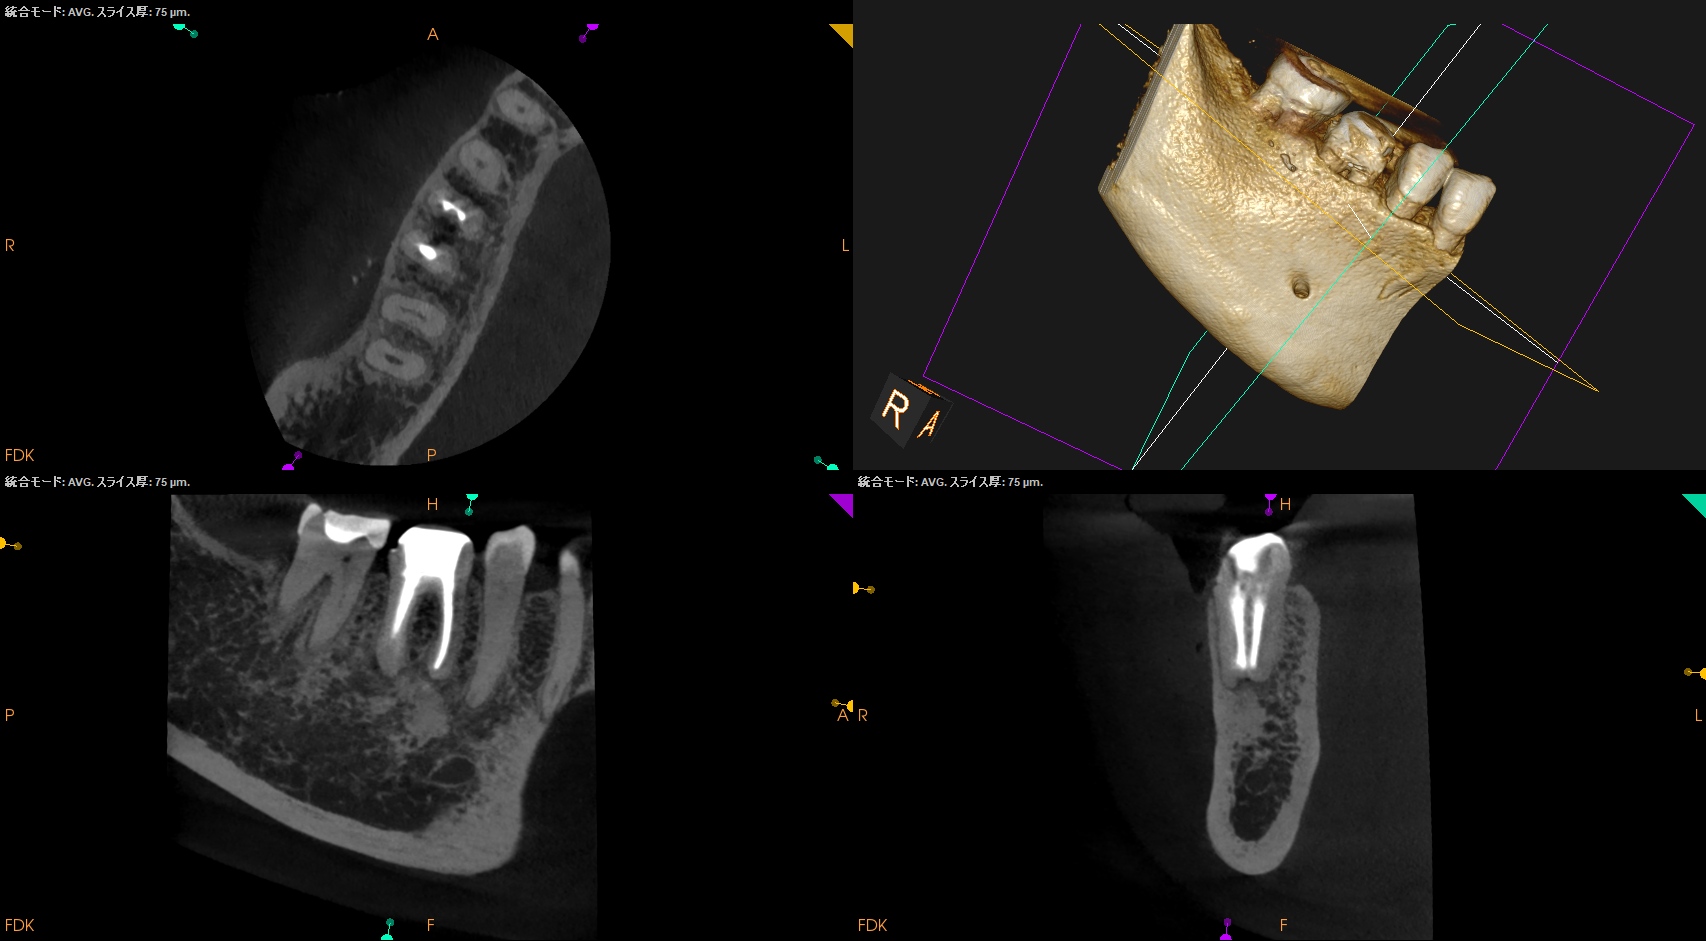

術後にPA, CBCTを撮影した。

MB

ML

D